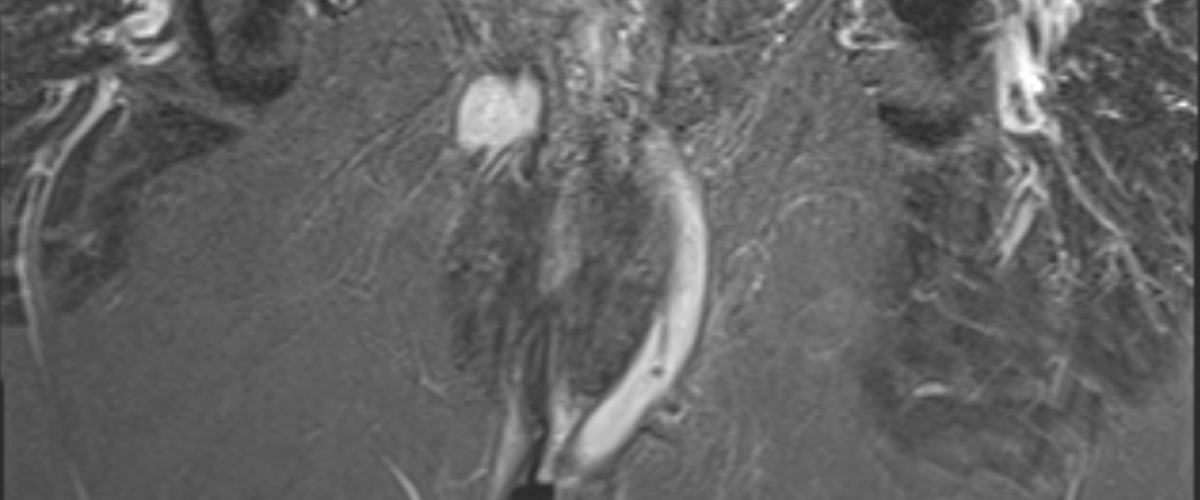

Affecting up to 30-40% of patients, they are associated with pain, leakage, and repeated interventions, often persisting for years despite intensive medical and surgical treatment. For patients, this means a profound impact on quality of life and daily functioning. For clinicians and researchers, it remains an area of urgent unmet need — where innovation in therapies, imaging, and outcome measures is essential to move care forward.

Achieving fistula closure while preserving continence remains difficult.

Even after surgical intervention or biologic therapy, recurrence rates remain high.

Many patients undergo multiple procedures and years of follow-up.